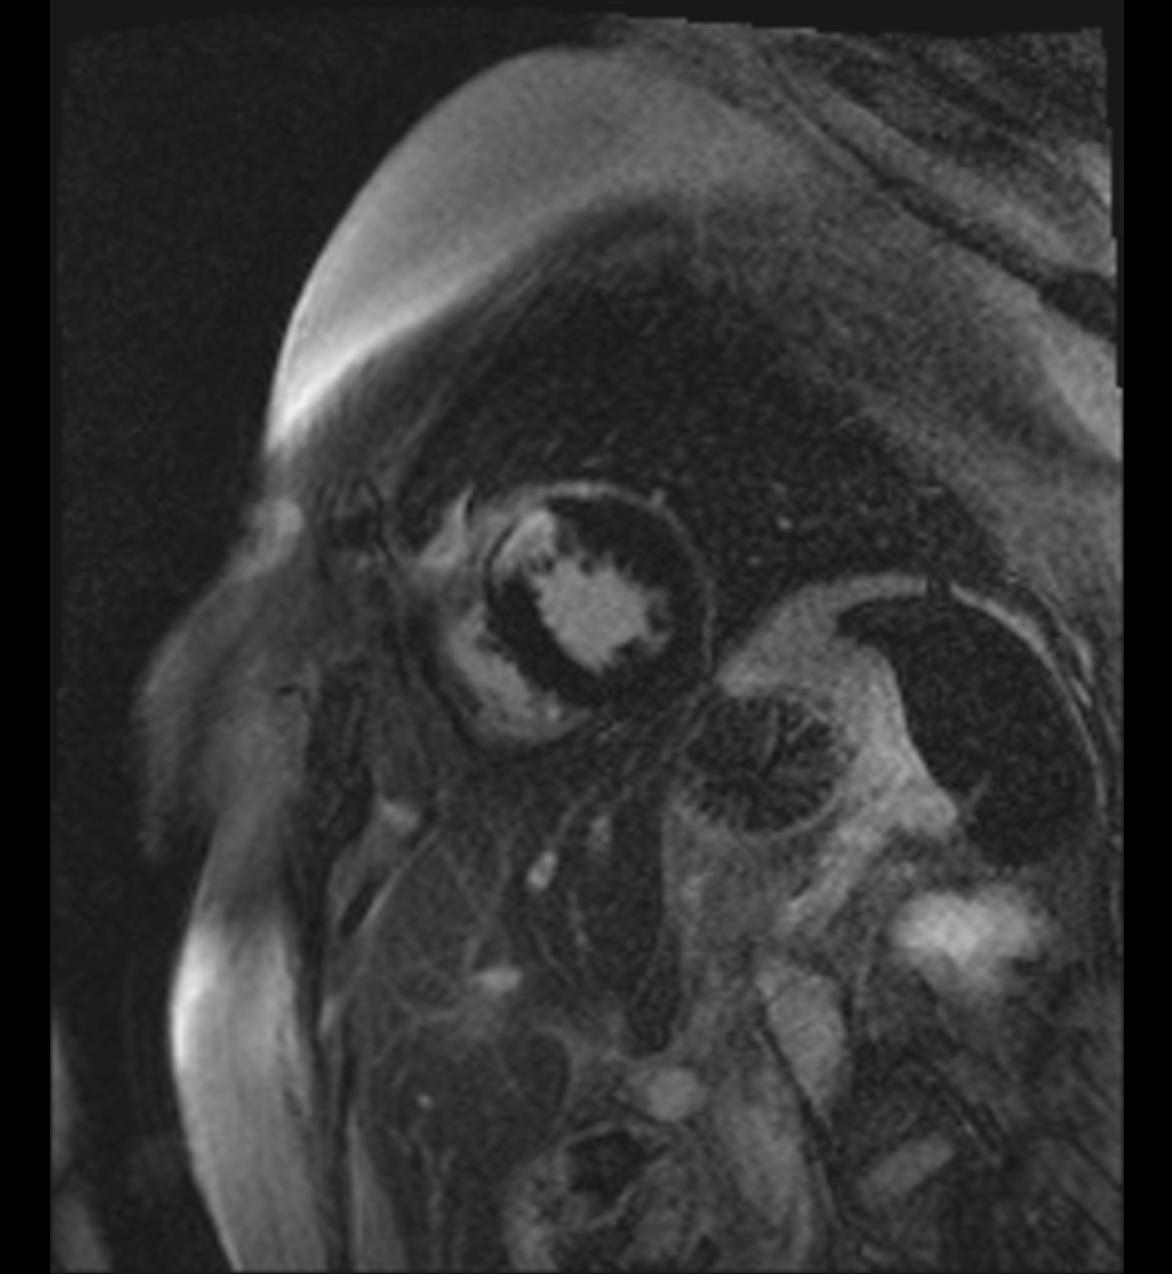

Die Patientin muss den Oberkörper im Untersuchungsraum ganz freimachen. Eine exakte Lagerung in Bauchlage ist hier besonders wichtig. Der Oberkörper wird direkt auf, die beiden Brüste, die immer im Seitenvergleich untersucht werden, direkt in die Spule hineingelagert und ausgepolstert. Da im Rahmen der Bildnachverarbeitung die Bildserien vor der intravenösen Kontrastmittelgabe von denen danach subtrahiert werden, ist es besonders wichtig, vollständig ruhig zu liegen, um keine Subtraktionsartefakte zu erhalten, die die Bildauswertung erschweren oder unmöglich machen.